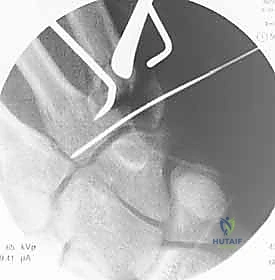

- صور الأشعة السينية المتخصصة (X-Rays): لا يكتفي الدكتور بالصور التقليدية، بل يطلب وضعيات تصوير خاصة (مثل الوضعية المائلة Oblique View بـ 30 درجة) التي تظهر قاعدة المشط بوضوح وتكشف الخلع الخفي.

تُجرى العملية غالباً تحت التخدير الموضعي للذراع (Brachial Plexus Block) أو التخدير العام. يتم تعقيم اليد وتجهيز جهاز الأشعة السينية داخل غرفة العمليات (C-arm) لمراقبة الخطوات مباشرة.

* أسلاك كيرشنر (K-wires): أسلاك معدنية دقيقة يتم إدخالها عبر الجلد لتثبيت عظم المشط بعظام الرسغ المجاورة. تُزال هذه الأسلاك في العيادة بعد 4 إلى 6 أسابيع.